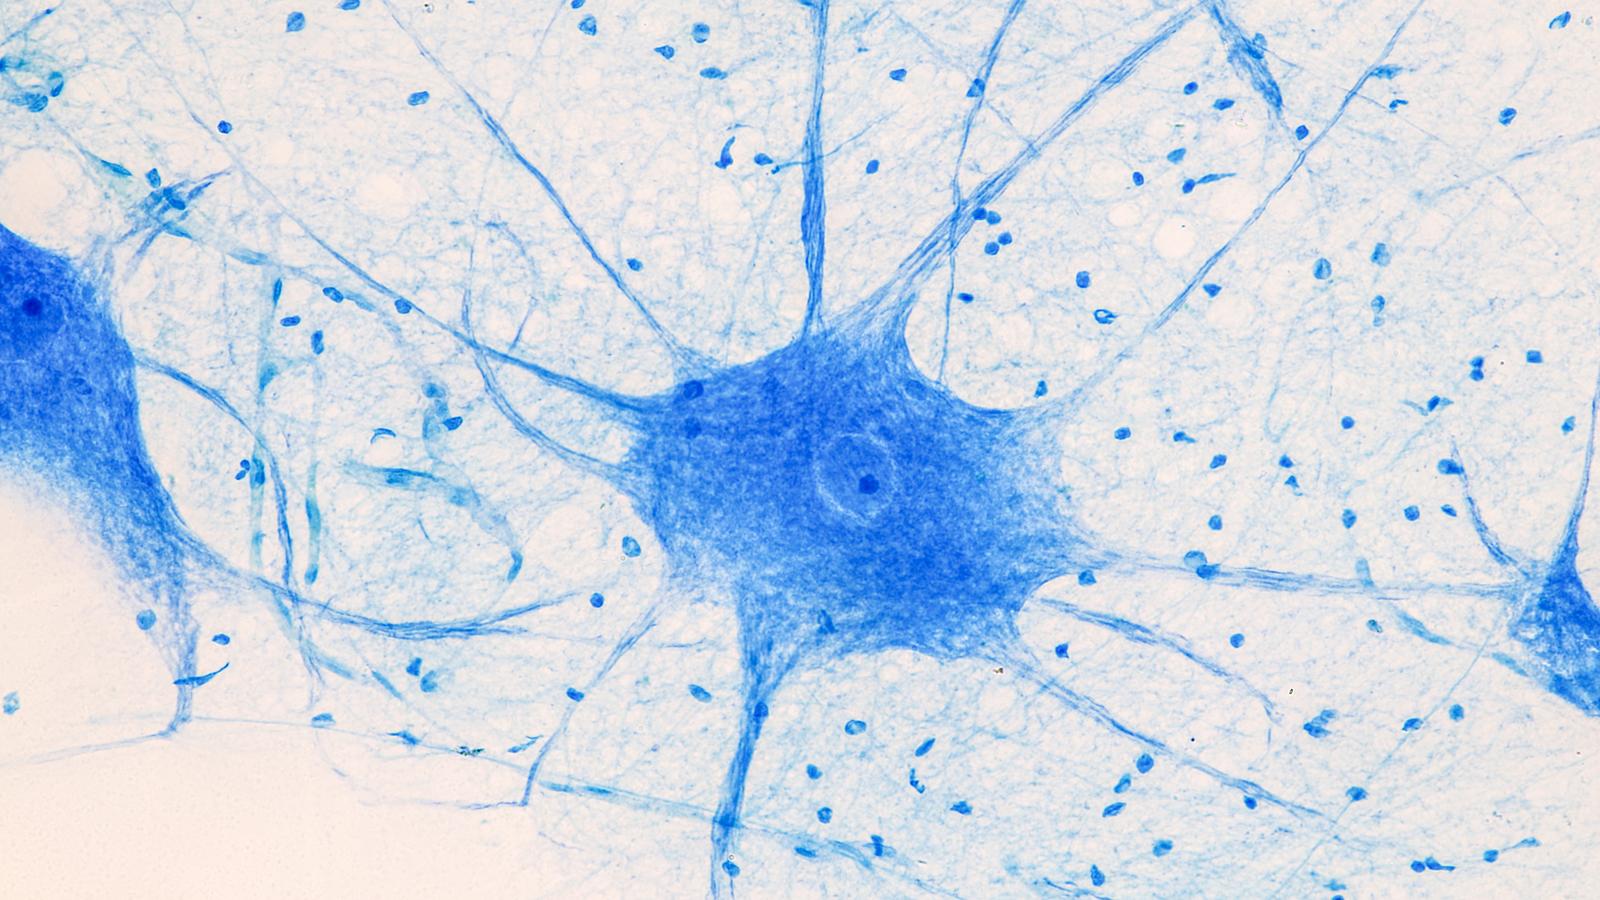

Das Gehirn ist zentral für unsere physische, mentale und soziale Gesundheit. Gleichzeitig sind wir mit kontinuierlich wachsenden, enorm hohen gesundheitlichen, wirtschaftlichen und psychosozialen Belastungen durch neurologische Erkrankungen konfrontiert. Um diese Belastungen aktuell und zukünftig zu reduzieren, muss neben der Diagnostik und der Therapie vor allem die Prävention neurologischer Erkrankungen deutlich intensiviert werden. Und: Gehirngesundheit ist weit mehr als nur das Fehlen oder die Verhinderung einer neurologischen Erkrankung. Sie beeinflussende Faktoren – über unsere gesamte Lebensspanne – bedürfen breiter Aufklärung und aktiver Förderung.

Die Gehirngesundheit zählt zu den größten präventivmedizinischen Herausforderungen des 21. Jahrhunderts.